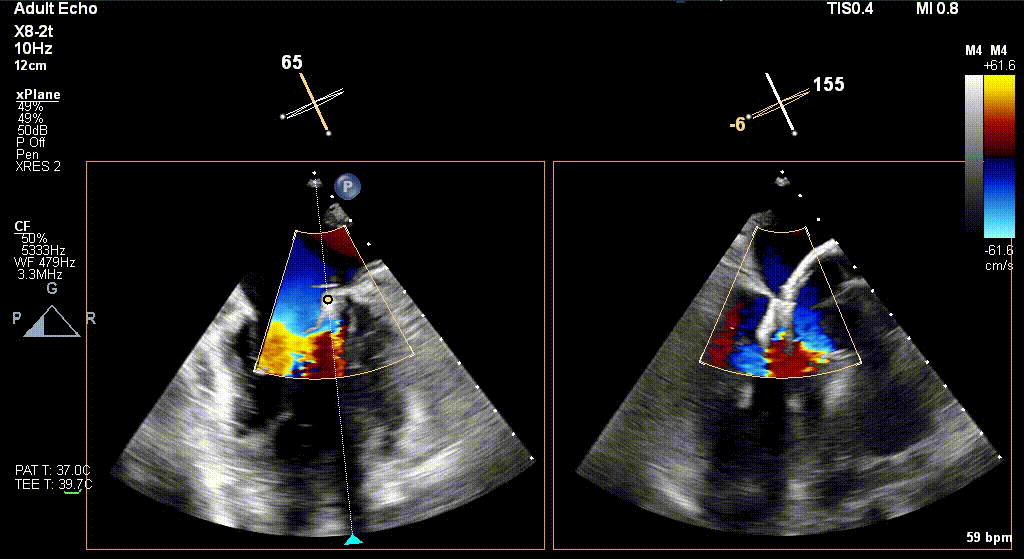

经食道超声引导后,王建安教授将二尖瓣夹NTR夹取C1区瓣叶,准确成功捕获C1前叶和后叶反流最严重区域,并予夹合。使二尖瓣在收缩期由大的单孔变成一大一小的双孔,显著减少了二尖瓣反流。

反复测试二尖瓣夹的稳定性,食道超声复查提示二尖瓣夹C1区反流有效改善,术后反流量由术前的4+变为术后的<1,遂精准释放二尖瓣夹。